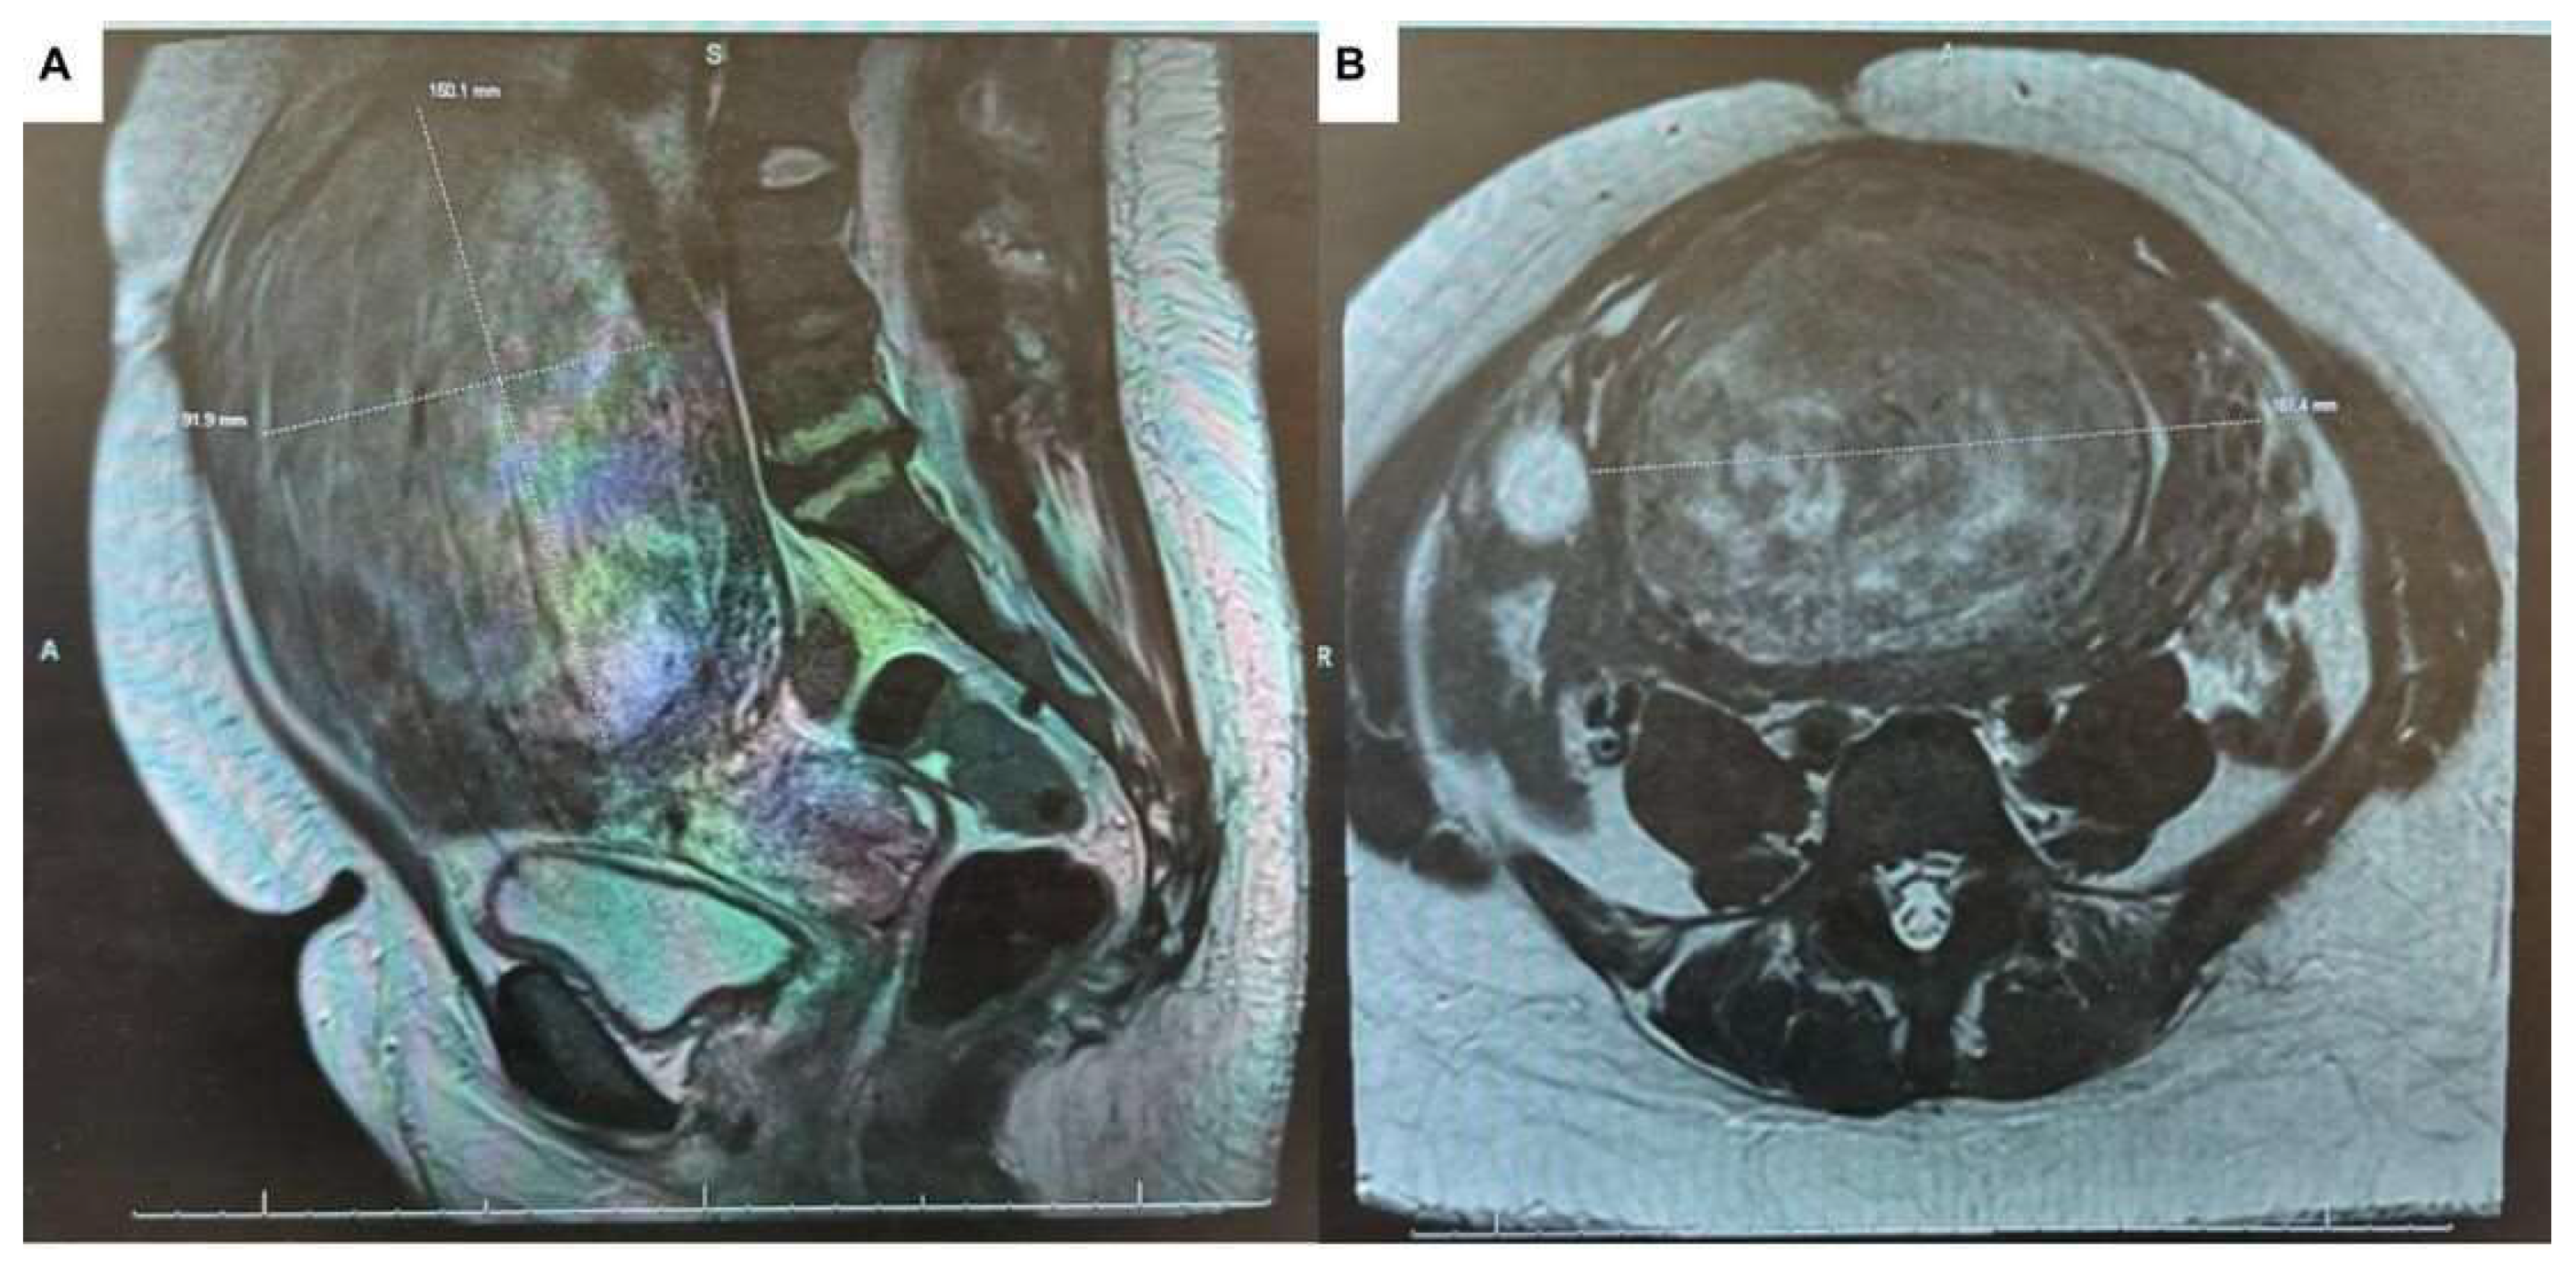

2. Case Presentation